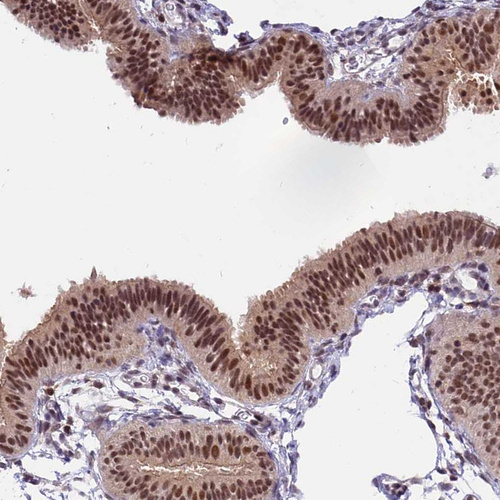

Immunohistochemical staining of human Fallopian tube shows strong nuclear positivity in glandular cells.